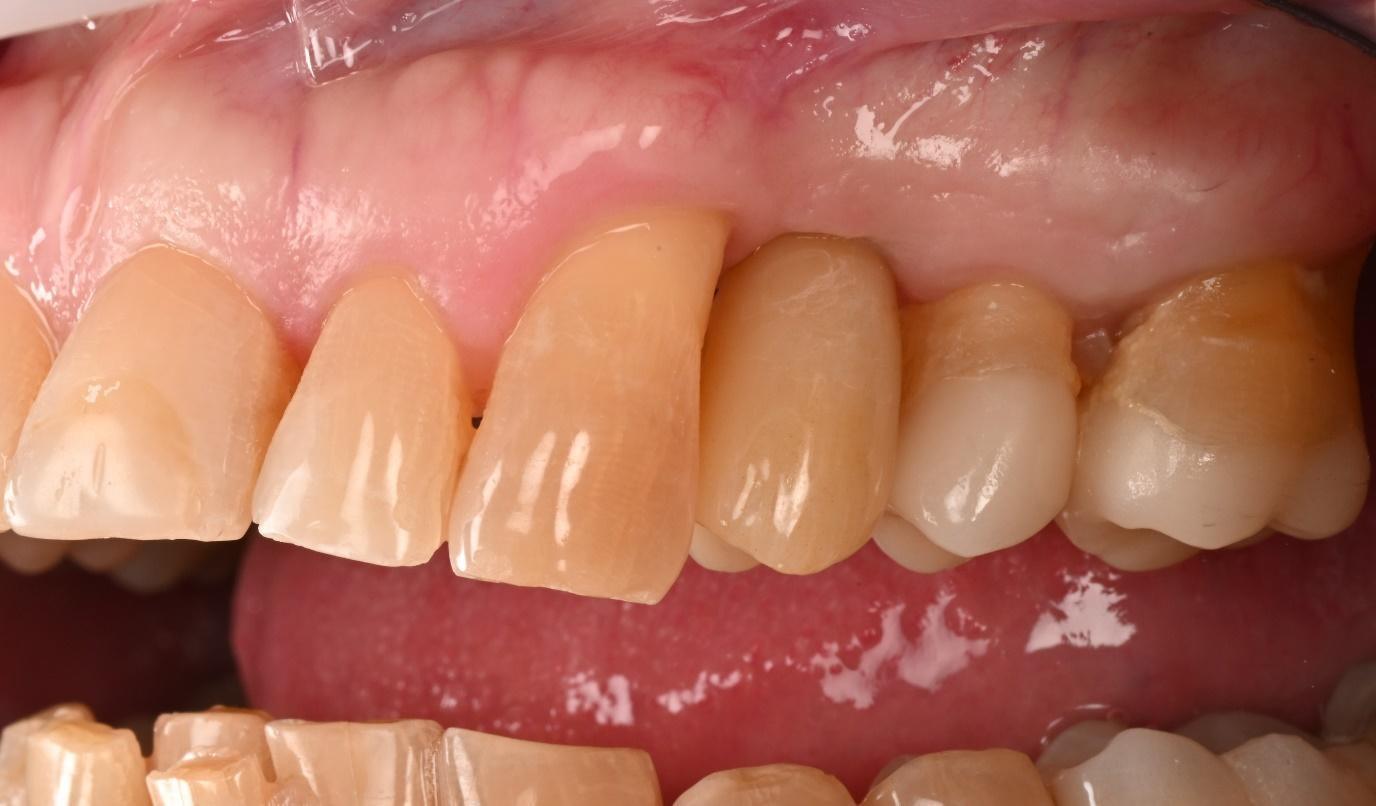

The successful completion of the implant treatment was evaluated based on aesthetics, function, and patient satisfaction.

The implant-supported crown seamlessly integrated with the patient's natural dentition, and the patient reported excellent comfort and function.

A radiographic assessment confirmed the proper integration and positioning of the implant.